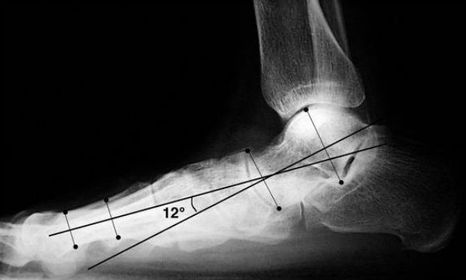

What is this angle called? What foot type does it indicate? | Talar - 1st MT or Meary's Angle Pes plano-valgus |

What is this angle called? What foot type does it indicate | Talar - 1st MT or Meary's Angle Pes cavo-varus |